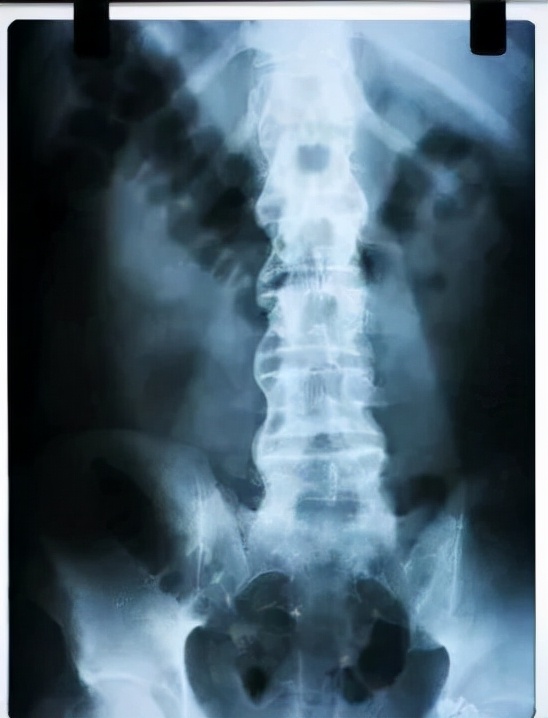

人类在20世纪30年代才认识到,几乎所有强直性脊柱炎患者都存在X线骶髂关节炎,从此,X线骶髂关节炎成为该病诊断的必要条件。

但后来发现部分患者X光检查但却没发现骶髂关节破坏,但在磁共振(MR)下却能看到活动性炎症征象。

2009、2011年,国际脊柱关节炎评估组又提出了中轴型脊柱关节炎,包括强直性脊柱炎、放射学阴性中轴型脊柱关节炎,它们在临床中表现为多种症状,常难以识别,导致诊断延迟、漏诊或误诊。